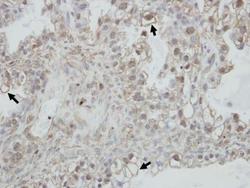

- Immunohistochemical analysis of paraffin-embedded human ovarian cancer, using PCDHGC4 (Product # PA5-31382) antibody at 1:100 dilution. Antigen Retrieval: EDTA based buffer, pH 8.0, 15 min.